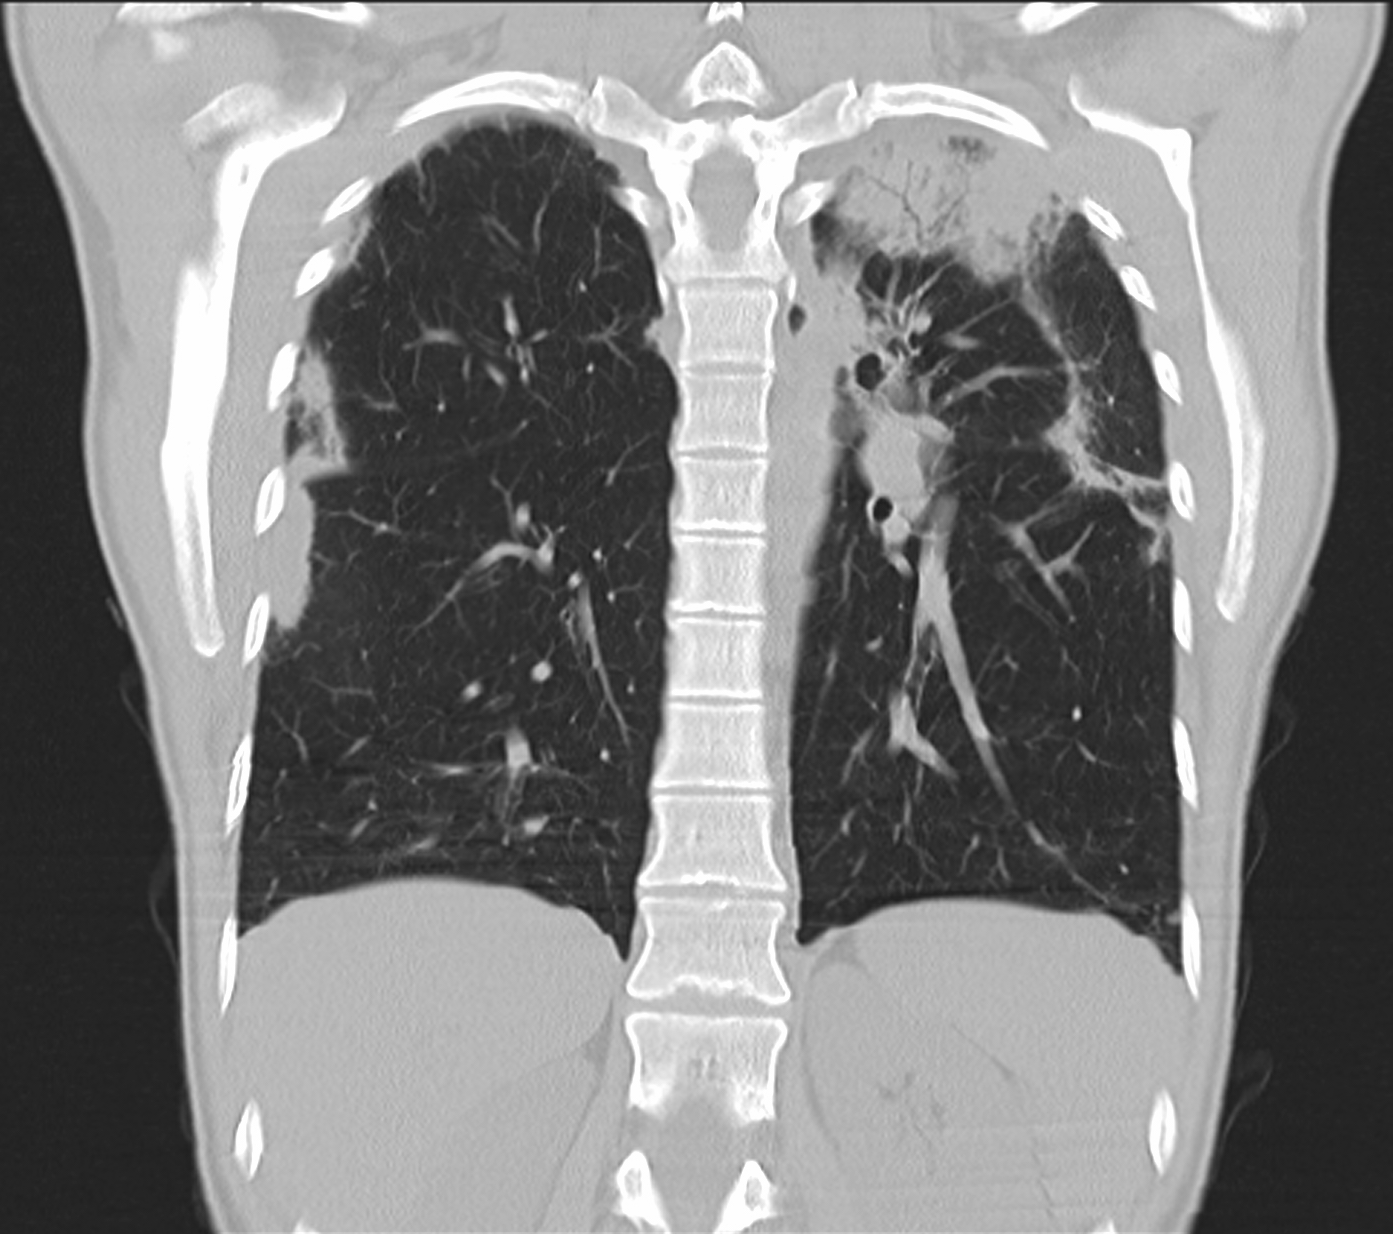

2b. Atelectasis, left upper lobe. CECT, coronal reconstr. (by the contribution of Zsuzsanna Monostori, MD, PhD)

3b: Multiple lung metastasis, CT lung window (axial, coronal reformat)

3c, coronal reformat

70 year old man, colon tumor.

Radiograph: Bilateral extensive, confluating patchy-nodular shadowing with diffuse reticular pattern. The diaphragm contour is partially blurry bilaterally: lymphangiosis carcinomatosa.

CT: Numerous 1-6 cm round and irregular, lobulated-spiculated contrast enhancing lesions in both lungs, everywhere sporadically.